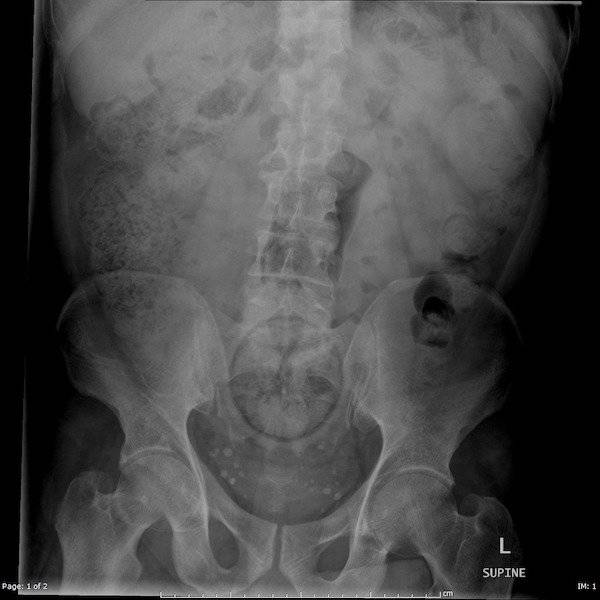

#10 Miehen jumissa oleva seksilelu ja pihdit, joilla hän yritti saada sen pois